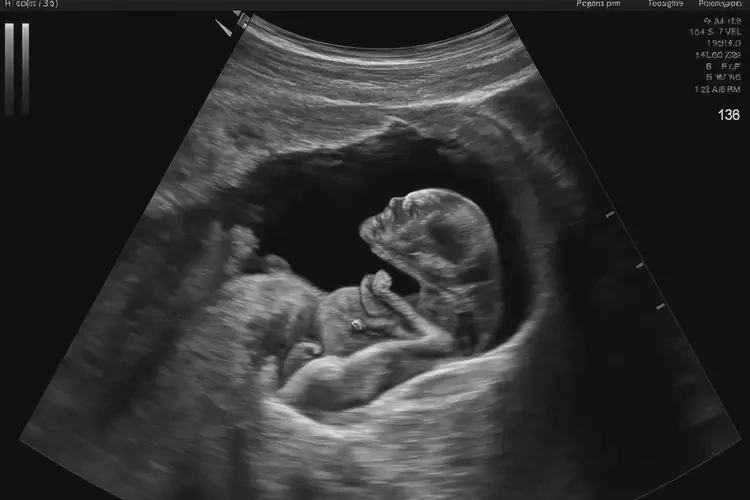

懷孕第37周胎心136正常嗎

136次/分鐘

懷孕第37周,胎兒的胎心在136次/分鐘是正常的。胎心率是指胎兒心臟每分鐘跳動的次數(shù),通常在120-160次/分鐘之間被認為是正常的。在懷孕的不同階段,胎心率可能會有所變化,但只要在正常范圍內(nèi),就無需過于擔(dān)心。

懷孕第37周胎心136正常嗎(圖1)